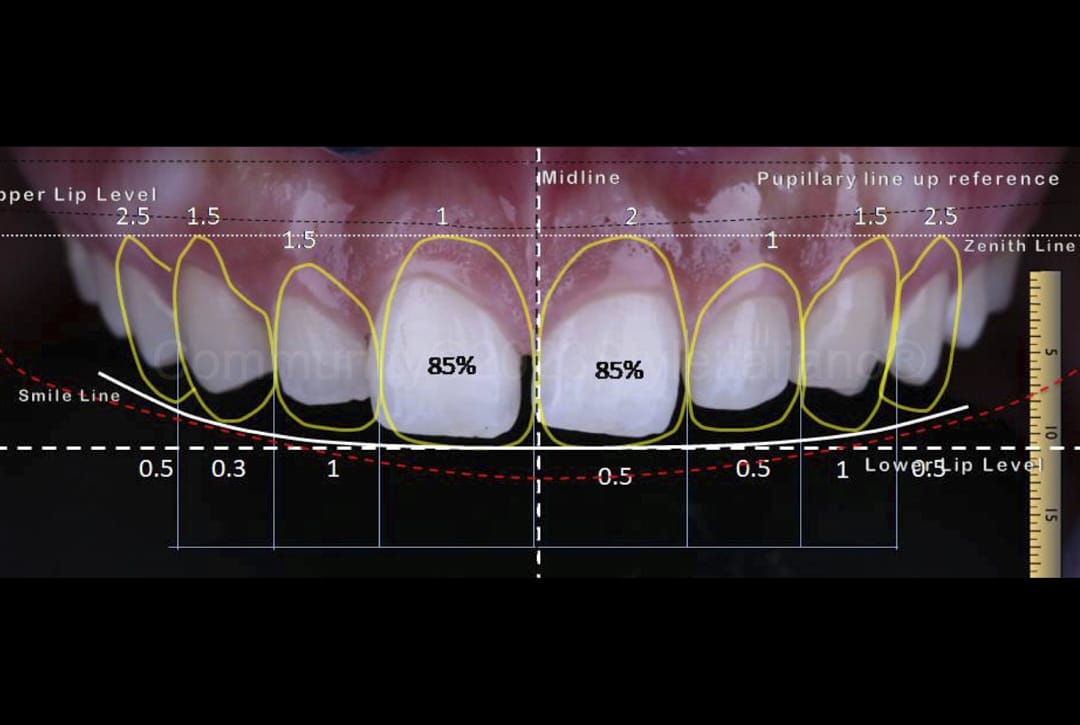

A comprehensive makeover combining veneers, crowns, and gum contouring to harmonize your smile with your facial features.